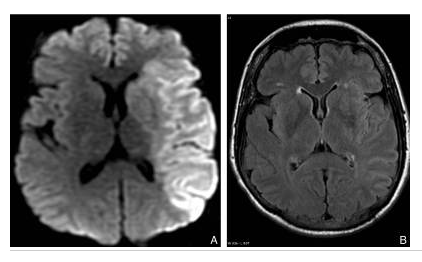

Signes d’AVC ischémique en phase aiguë en IRM.

IRM réalisée à 3 heures de l’installation du déficit. La coupe axiale pondérée en diffusion

(A) montre très nettement une plage en hypersignal à contours bien limités touchant la substance blanche et la substance grise et correspondant au territoire superficiel et profond de l’artère cérébrale moyenne gauche.

Ces anomalies sont à peine visibles sur la séquence FLAIR (B).